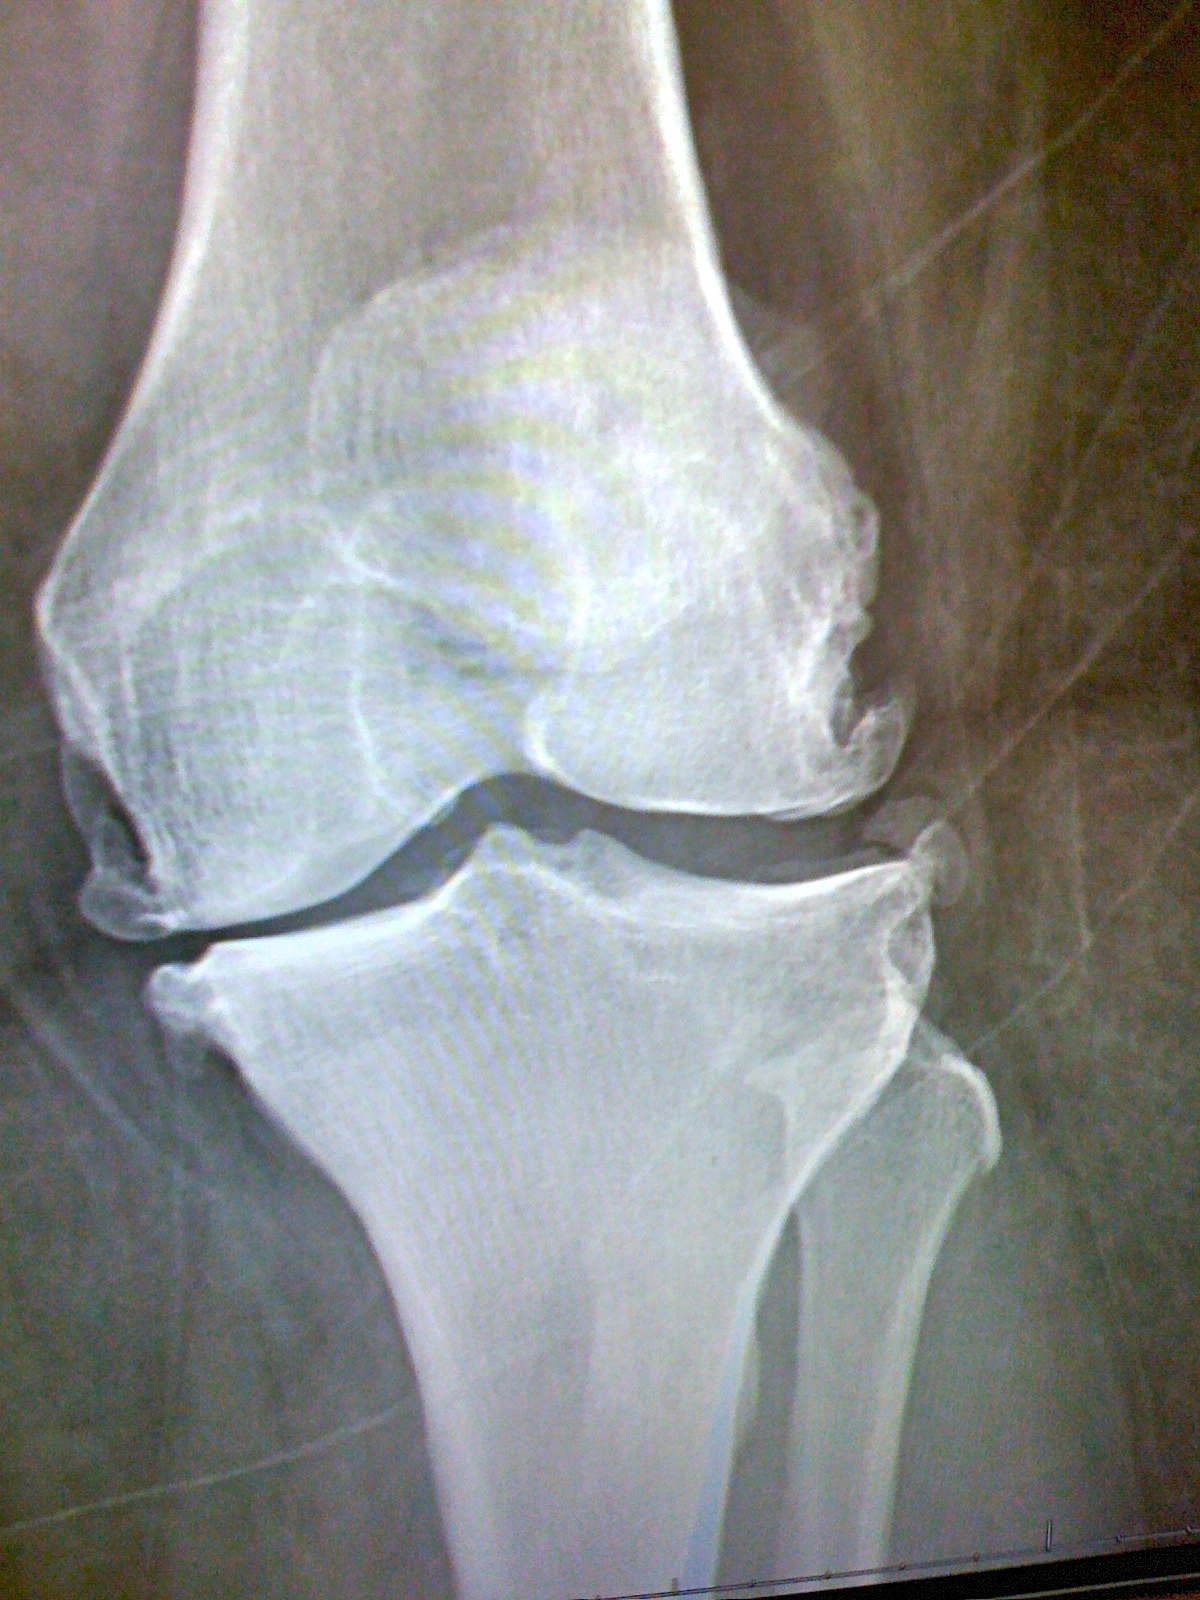

I went to my ortho doctor recently and he did some new xrays. If you’ve ever wanted to see what advanced arthritis of the knees looks like- here you go!

I took a picture of my xrays with my phone. As you can see, I’m bone on bone.

And see those little hooks on the ends of my bones? Those are calcium deposits from the arthritis. The round things are my knee caps. Apparently they are higher than they should be. Looks like I’ve got coasters on my thighs!